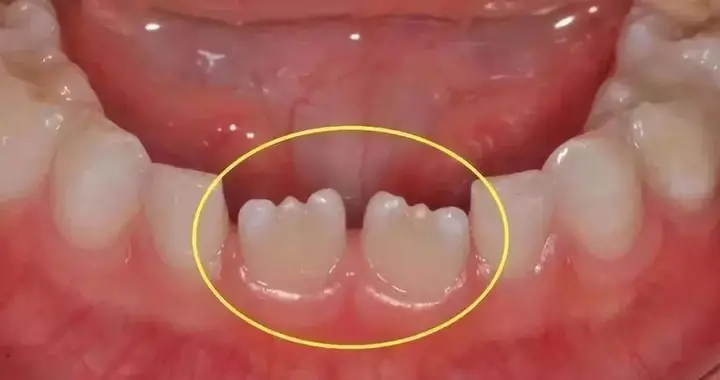

小孩牙齿为什么呈锯齿状?